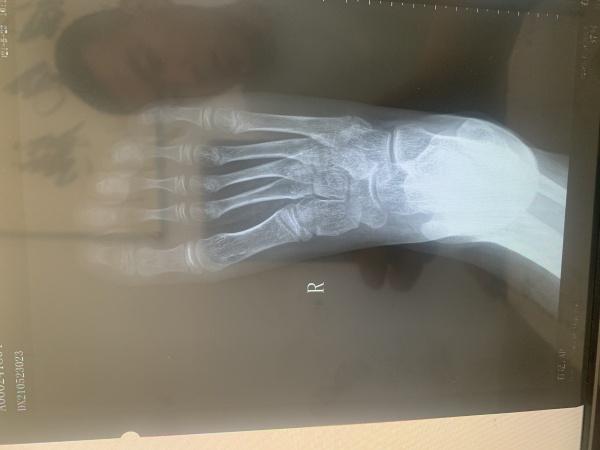

九岁儿童第5跖骨基底部各位大神帮忙看一下

发病一周 有没有手外伤孩子已经表达不清楚,本人考虑骨骺,以前没有遇见过想咨询一下各位大神,这种情况该如何恢复。儿童9岁

分明是右足,为什么会诊断为手外伤,第5跖骨基底部外侧为骨骺而已!

骨骺未愈合。。。。